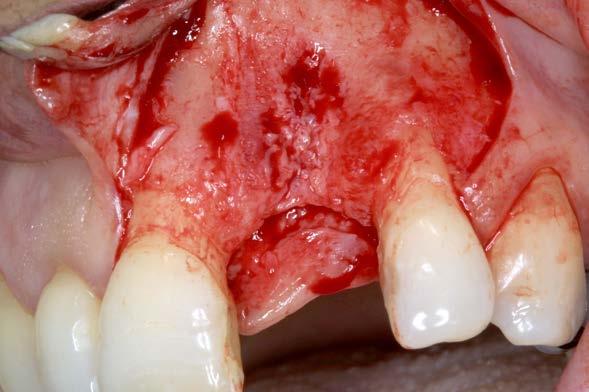

Figuras 1 y 2. Imágenes iniciales de la paciente. Se observa el diente en posición 21 con un cambio de color evidente y supuración espontánea a través del surco gingival. Asimismo, se aprecia el impacto estético del cambio cromático en la sonrisa y en el aspecto del frente anterosuperior.

Caso clínico

Se presenta el caso de una paciente femenina de 47 años de edad al inicio del tratamiento, quien acude a consulta por dolor y supuración en el incisivo central superior izquierdo. En las imágenes iniciales se observa un diente con un cambio de color llamativo y una supuración espontánea a través del surco gingival (Figura 1). Esta alteración cromática, además de reflejar un problema asociado al diente, afecta de manera significativa la estética del frente anterior, como se aprecia en la imagen de sonrisa (Figura 2).

El diente había sufrido un traumatismo durante la infancia de la paciente y, tras la pérdida de vitalidad pulpar,

Rehabilitación de incisivo central con implante diferido y sobrecorrección con injerto óseo particulado y PRGF-Endoret

se realizó un tratamiento de apiconformación que, al momento de la revisión, mostraba signos de fracaso, con evidencia de infección y clínica sugestiva de fractura radicular (Figura 3).

Como primera fase del tratamiento, se procedió a la exodoncia del diente y a la regeneración del alveolo con PRGF-Endoret, tras un legrado minucioso del lecho. Una vez completada esta regeneración, a las 14 semanas

se llevó a cabo la fase quirúrgica para la colocación del implante.

Se elevó un colgajo a espesor total con márgenes amplios (Figuras 4 y 5), lo que permitió recolectar hueso autógeno de las áreas adyacentes mediante un rascador óseo. Este abordaje facilitó además un cierre primario sin tensión tras la colocación del implante y la sobrecorrección. El hueso obtenido se mantuvo en PRGF-Endoret,

Figuras 4 y 5. Elevación del colgajo, donde se aprecia el lecho alveolar regenerado y la zona donante situada por encima del ápice del diente 11.

fracción 2 sin activar, hasta el momento de su utilización en la zona receptora, preservando la vitalidad celular y mejorando la manejabilidad del injerto particulado (Figura 6). Posteriormente, este hueso se unió al recolectado durante el fresado biológico del lecho.10

El lecho implantario se preparó mediante fresado biológico, ajustado al tipo de hueso y a las dimensiones del implante planificado. A continuación, se procedió a la inserción del implante, que alcanzó un torque de inserción adecuado, permitiendo dejarlo en fase de cicatrización con el pilar

correspondiente colocado. Una vez colocado el implante y el pilar de cicatrización, se realizó una técnica de sobrecorrección vestibular con el injerto particulado inmerso en PRGF-Endoret, recubriendo toda la zona con una membrana autóloga de fibrina (fracción 1 activada y retraída). Se suturó con monofilamento no reabsorbible, sin tensión, para evitar el colapso del volumen vestibular que se buscaba ganar (Figuras 7 a 10). Como provisional se empleó el propio diente de la paciente, ferulizado a los adyacentes con resina, a modo de puente Maryland (Figura 11).

un cone beam de control para valorar el estado de un tratamiento endodóntico en la pieza 26; en el corte seccional correspondiente al implante se aprecia una estabilidad completa, con un volumen vestibular óseo significativo.

Estos hallazgos confirman el éxito del procedimiento quirúrgico y de la posterior carga progresiva, con un mantenimiento óptimo de los tejidos duros y blandos a lo largo de más de dos décadas (Figura 15). Los cambios entre el momento inicial y el final del tratamiento son evidentes, especialmente al comparar la imagen intraoral de la primera visita con la tomada a los 22 años, donde la mucosa que rodea al diente 21 —y posteriormente al implante— se muestra engrosada, en buen estado de salud y con una estética destacable. Asimismo, la comparación entre la radiografía inicial, que evidenciaba el fracaso del tratamiento de conductos del diente en posición 21, y la radiografía a los 22 años, que muestra el implante sin pérdidas óseas asociadas, resulta elocuente (Figuras 16 a 19).

Figuras 16 y 17. Comparación entre la imagen inicial —diente con cambio de coloración, encía inflamada y pérdida de grosor— y la obtenida a los 22 años, que muestra estabilidad y salud gingival con el implante.